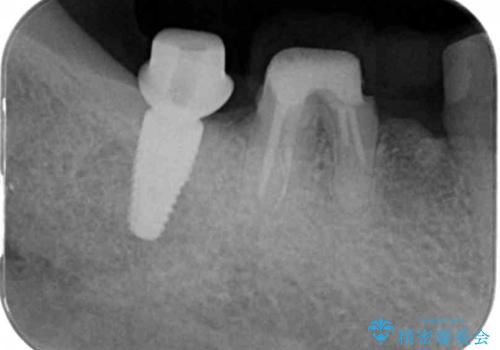

重度に吸収してしまった歯槽骨をしっかりと造成を行ったのちにインプラント治療を行ったので、安定した歯周環境にすることができました。